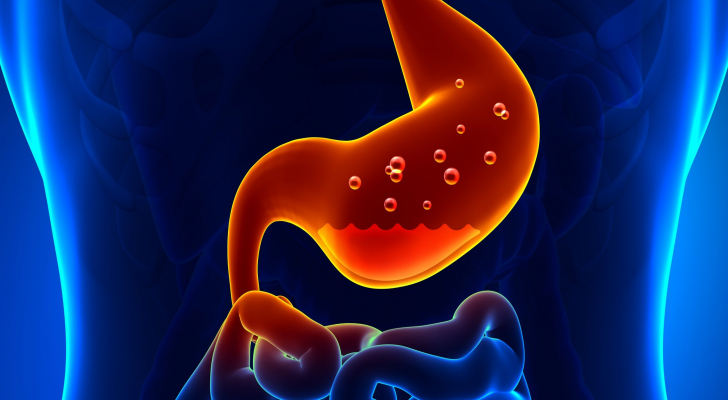

يعتبر الارتداد المريئي من أمراض الجهاز الهضمي، و الذي يحدث عندما يتدفق حمض المعدة بشكل متكرر الى المريء بسبب ارتخاء العضلة العاصرة التي تفصل بين المعدة والمريء والذي يمكن أن يسبب تهيج في بطانة المريء، حيث يعاني الكثير من الأشخاص من ارتداد الحمض من وقت لآخر بسبب وجود تغييرات في النظام الغذائي، فـ الارتجاع المعدي المريئي هو ارتداد حمضي خفيف يحدث لأكثر من مرتين في الأسبوع على الأقل.